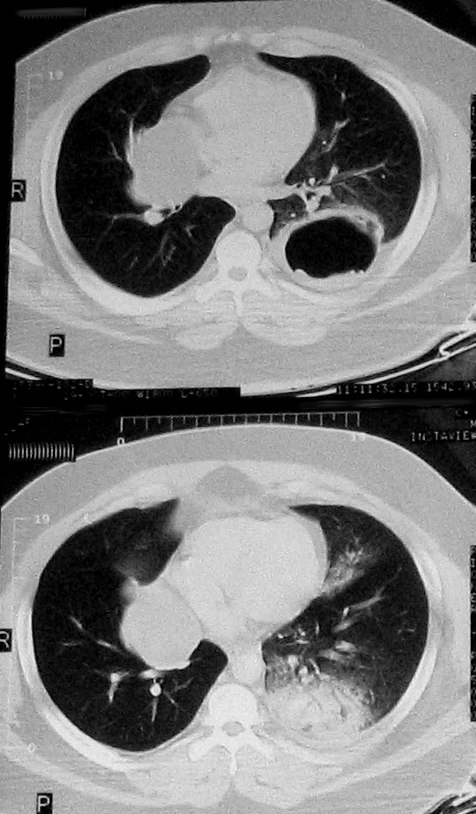

This 32 year-old female patient presented with a cough. Selected CT images show a cystic lung lesion with a moderate thickness wall, and a dependant wavy contour (the water-lily sign). A more caudad slice shows left lower lobe consolidation. The appearance is consistent with ruptured hydatid cyst. The water-lily sign represents dependant membranes within the cyst.

Consolidation is due to a vigorous inflammatory response to endobronchial spread of cyst contents.